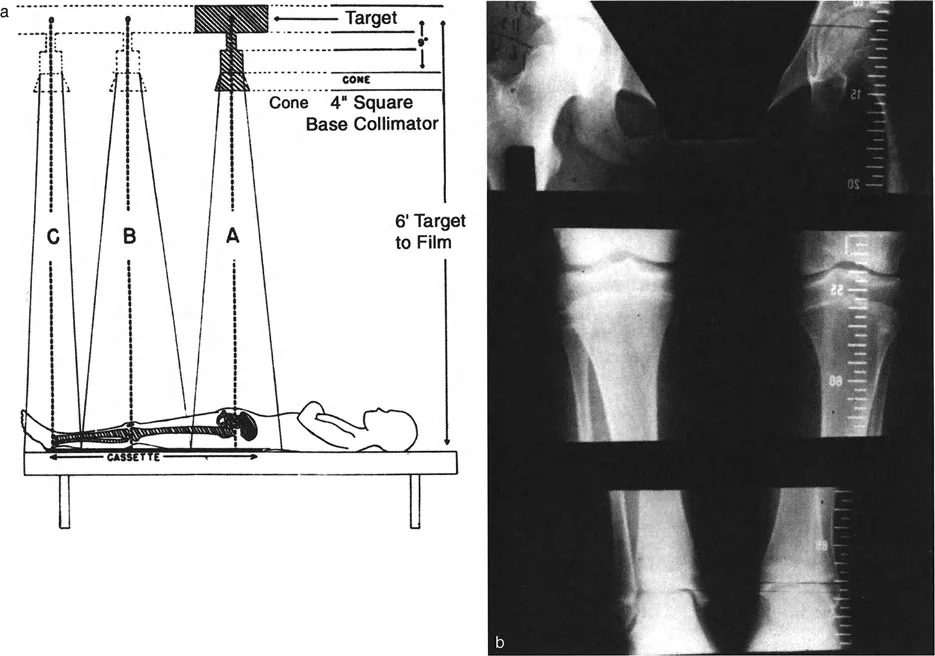

التقييم الإشعاعي: المعيار الذهبي

نظرًا لأن القياسات السريرية تحتوي على هامش خطأ واسع، يظل التقييم الإشعاعي هو المعيار الذهبي بلا منازع لتحديد كمية تفاوت الط